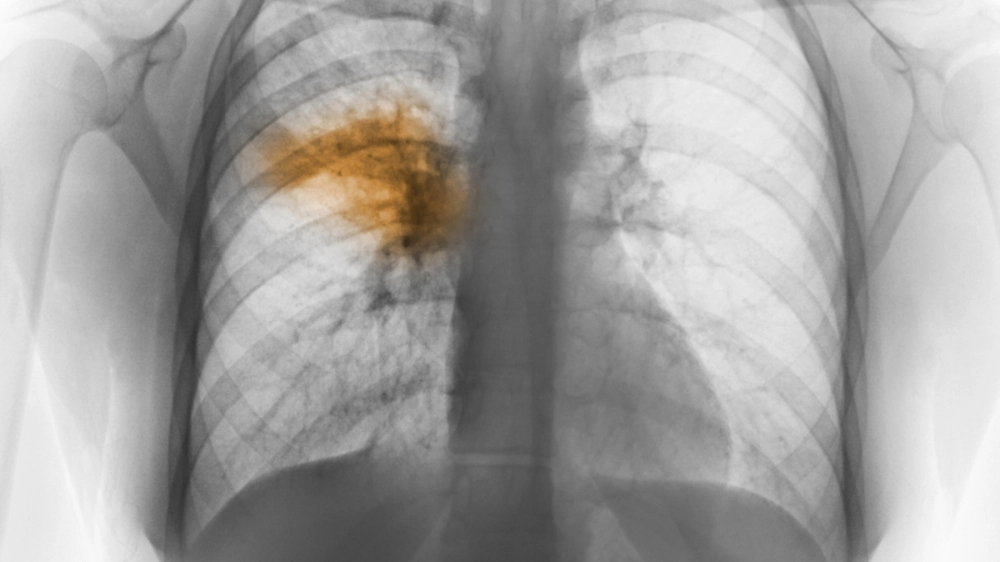

Hình ảnh tổn thương thùy phổi khi chụp X-quang phổi